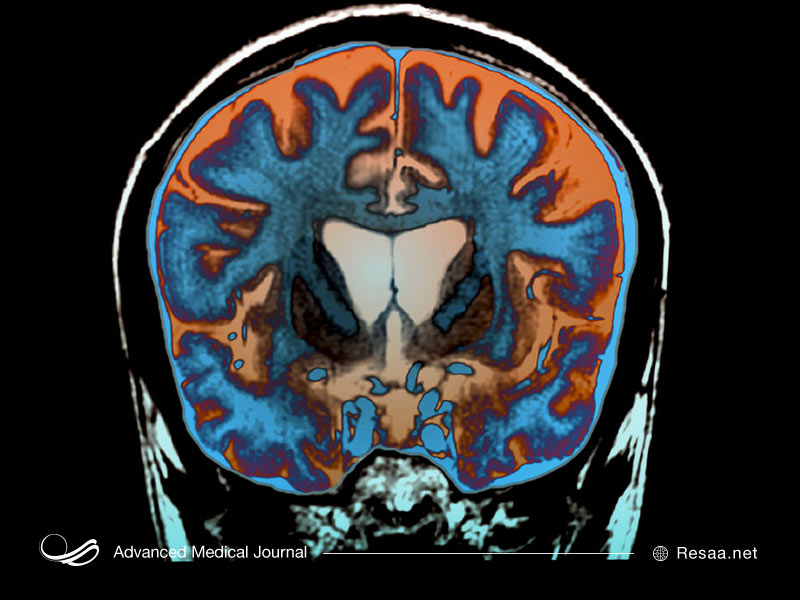

تصویربرداری تشخیصی: در برخی موارد، به خصوص اگر سابقه خانوادگی و آزمایش ژنتیکی فرد بی نتیجه باشد، پزشک ممکن است تصویربرداری از مغز را توصیه کند، مانند توموگرافی کامپیوتری (CT) یا به احتمال زیاد تصویربرداری رزونانس مغناطیسی (MRI).

با پیشرفت بیماری، این اسکنها به طور معمول انقباض جسم مخطط و قسمتهایی از قشر و بزرگ شدن حفرههای پر از مایع در مغز به نام بطنها را نشان میدهند. این تغییرات لزوماً نشان دهنده HD نیستند، زیرا ممکن است در سایر اختلالات نیز رخ دهند. برعکس، یک فرد میتواند علائم اولیه هانتینگتون را داشته باشد و هنوز هم یافتههای طبیعی در اسکن CT یا MRI او دیده شود.